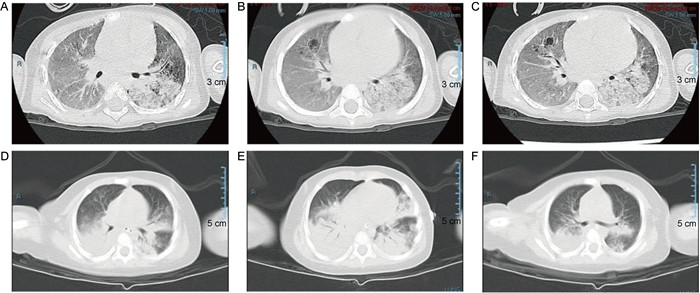

A~C: 病例1肺部CT征象,两肺可见斑片状、片状密度增高模糊影,以左肺下叶为主(A),可见支气管充气征(B),可见囊状薄壁透亮影(C)。 D~F: 病例2肺部CT征象,两肺可见斑片状、片状密度增高模糊影,以双肺下叶为主(D),可见支气管充气征(E),右侧胸腔见弧形液性密度影(F)。 图 1 惠普尔养障体感染患儿肺部CT征象 Fig. 1 The pulmonary CT findings in children with Whipple disease and associated infections |

1.1 病例1资料患儿女,3岁5个月,因“咳嗽、发热1周,气促、发绀12 h”急诊入院。患儿2岁时在外院诊断为重度营养不良,无激素、抗生素等长期用药史。入院体格检查:体温39.3 ℃,呼吸197次/min,心率75次/min,血压8.93/4.67 kPa,体质量10 kg,身长89 cm。神清而靡,鼻翼扇动,胸腹式呼吸,见吸气性三凹征,动脉血氧饱和度(oxygen saturation in arterial blood,SaO2)58%,双肺闻及湿啰音及哮鸣音。心音有力,律齐,无杂音。腹软,腹壁脂肪消失,肝脾肋下未触及,肠鸣音正常。神经系统检查无异常。辅助检查具体如表 1及图 1A~C所示。

1.2 病例2资料患儿男,5月龄,因“发热、声音嘶哑27 h,气促11 h”急诊入院。体格检查:体温39.6 ℃,呼吸200次/min,心率60次/min,血压10.67/4.93 kPa,体质量8 kg,SaO2 90%(未吸氧)。患儿神清,前囟平软,咽部充血,呼吸急促,见轻度吸气三凹征,双肺闻及喉喘鸣,心律齐,心音有力,未闻及杂音。腹部检查无异常,神经系统检查未见异常。辅助检查具体结果如表 1及图 1所示。